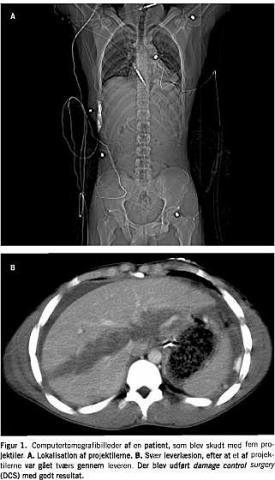

Mortaliteten er ofte meget høj ved store, akutte operationer hos multitraumatiserede patienter [1-3]. Dette skyldes en livsfarlig triade af metabolisk acidose, koagulopati og hypotermi [4]. Da hypotermien og forstyrrelser af koagulationen synes at være afgørende, har man forsøgt at ændre behandlingsforløbet ved en ændret strategi, kaldet damage control surgery (DCS). Dette princip er beskrevet næsten samtidig af forskellige grupper i begyndelsen af 1990'erne [1, 2, 5-8]. »Den afbrudte laparotomi«, eller »damage control surgery« blev kendt som princip, efter at Rotondo et al i 1993 påviste en overlevelse på over 70% hos en gruppe multitraumatiserede patienter, som blev behandlet med DCS [1, 2]. Disse 13 patienter havde foruden multiple kvæstelser også koagulopati, hypotermi og acidose [1, 2]. DCS-strategien angives at omhandle seks faser: Fase 0-5 [3]. De forskellige faser består af: fase 0) præhospitalbehandling og tidlig patientudvælgelse til DCS, fase 1-2) laparotomien med vurdering af behovet for DCS og udførelsen af den midlertidige lukning, fase 3) stabilisering på intensivafdeling, fase 4) endelig operation og rekonstruktion og fase 5) til sidst definitiv lukning af abdomen [3, 8-13]. I forskellige studier er det vist, at DCS hos multitraumatiserede patienter antages at nedsætte mortaliteten betydeligt [1, 2, 9, 12-17]. Vi har fundet det af interesse at gennemgå litteraturen for at se, om man efter ti års anvendelse af DCS-metoden kan opstille nogle behandlingsanbefalinger og resultater ved anvendelsen (Figur 1 ).